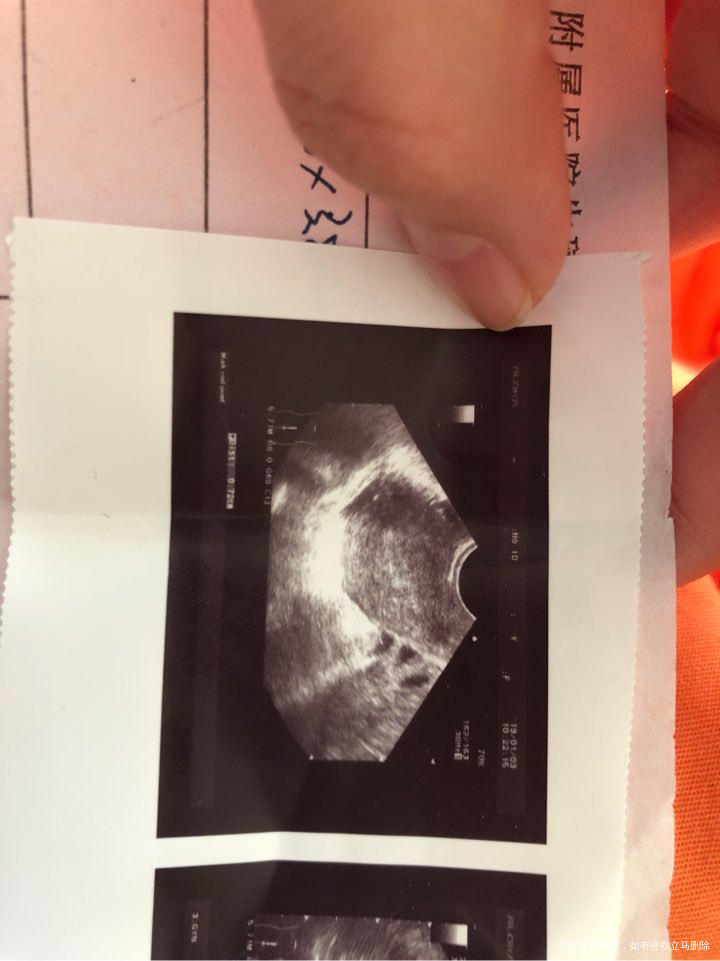

🐰包子 回复 周朋朋:是内膜上有问题吗

2楼内膜是正常的,放心吧,做宫腔镜检查子宫内的情况,排出粘连等情况,没事就可以试管的,祝好孕,孕前3个月至孕3个月口服叶酸预防胎儿脑神经畸形!如果我的回答对你有帮助,请采纳!谢谢

🐰包子 回复 姬晓丽:可以不做宫腔镜,直接移植吗,我想尽快移植

3楼内膜是正常的,移植前必须做的检查,看宫内情况是否利于着床。排除一下。别担心。记得帮忙点击采纳吧,谢谢啦!